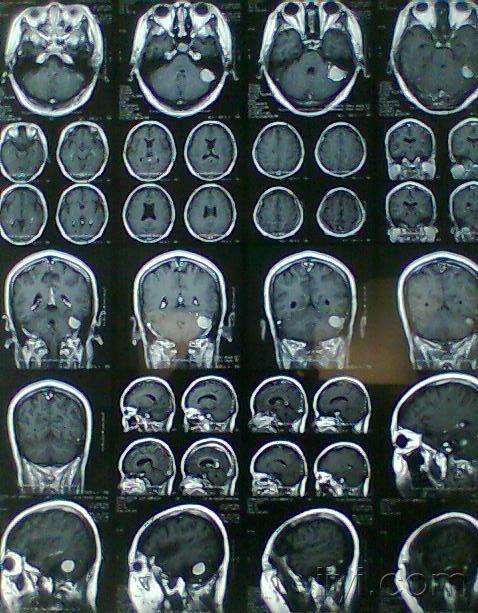

【请教】头颅mr--非常罕见,爆米花样增强,这是什么肿瘤?

图片尺寸1076x859